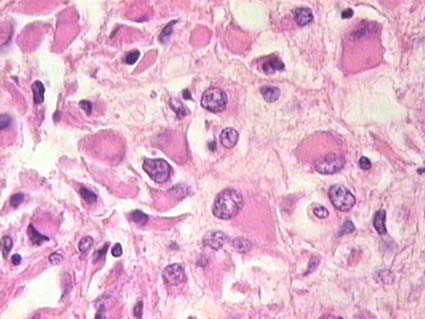

Figura 34. Tumor de Wilms, componente epitelial en medio del cual se identifican células grandes, muy llamativas, con mitosis claramente atípicas, multipolares, indicativas de anaplasia. Es necesario evaluar la extensión y localización de las áreas con anaplasia para determinar si es focal o difusa (ver texto). (H&E, X300).

La anaplasia está asociada con mayor resistencia a la quimioterapia y no es un marcador de agresividad tumoral. Anteriormente se llamaba anaplasia focal a los tumores con <10% de campos microscópicos conteniendo características anaplásicas.